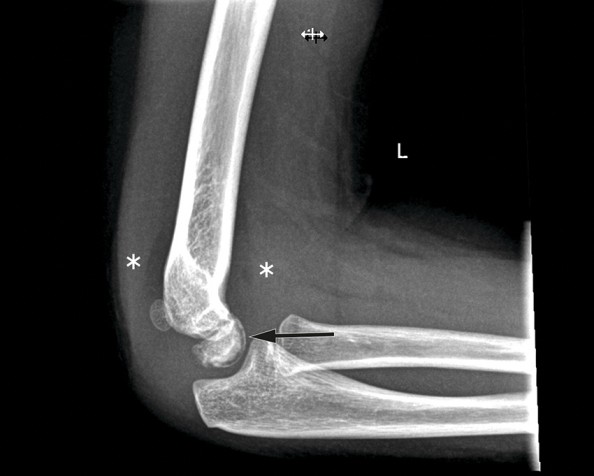

På røntgenbildet samsvarer oppklaringslinjen (markert med sort pil) med flere små gassbobler på samme sted på CT-bildet (hvit pil) - såkalt vakuumfenomen. Løftet fremre og bakre fettpute (markert med stjerner) er tegn på hydrops. Det er også litt ujevn benkontur ventralt i capitulum. Funn er typisk for Panners sykdom.

Røntgenbildet av venstre albue viser løftede fettputer som tegn på hydrops (markert med stjerner), men ingen synlig fraktur eller luksasjon. Det ses en tynn stripe med redusert bentetthet subkondralt i ventrale del av capitulum (sort pil), og på CT-bildet samsvarer linjen med flere små gassbobler på samme sted – såkalt vakuumfenomen. Det er også ujevn benkontur ventralt i capitulum. Funnene er typisk for Panners sykdom.

Bildene er av en jente i sen barnehagealder som kom til lege etter fire dagers sykehistorie med smerter og nedsatt bevegelighet i venstre albue uten kjent forutgående traume. Pasienten hadde hatt to episoder med subluksasjon av radiushodet, gjerne omtalt som pulled elbow, på samme side, sist for to år siden. Ved klinisk undersøkelse var hun lite smertepreget, men hadde 20–30° redusert passiv og aktiv ekstensjon i albueleddet samt lett redusert supinasjon. For øvrig var det normale funn ved undersøkelse.